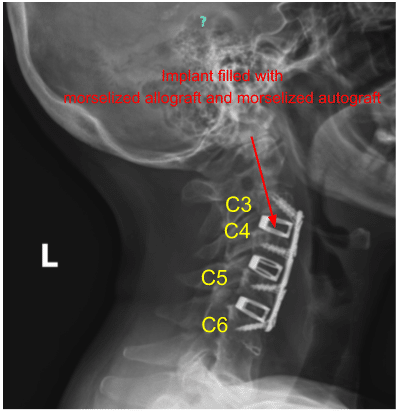

El sangrado epidural se controló fácilmente con Surgiflo y un suave taponamiento de algodón. Luego probamos el tamaño de nuestro implante y obtuvimos radiografías. Llenamos nuestro implante con un aloinjerto morselizado y un autoinjerto morselizado.

El sangrado epidural se controló fácilmente con Surgiflo y un suave taponamiento de algodón. Cuadramos el espacio del disco con el taladro de alta velocidad y preparamos el espacio del disco para la artrodesis. Luego probamos el tamaño de nuestro implante y obtuvimos radiografías. Llenamos nuestro implante con aloinjerto morselizado y autoinjerto morselizado.

El sangrado epidural se controló fácilmente con Surgiflo y un suave taponamiento de algodón. Cuadramos el espacio del disco con el taladro de alta velocidad y preparamos el espacio del disco para la artrodesis. Luego probamos el tamaño de nuestro implante y obtuvimos radiografías. Llenamos nuestro implante con aloinjerto morselizado y autoinjerto morselizado.

Medimos nuestra placa anterior, la colocamos sobre nuestros niveles de interés y la fijamos en su lugar. Obtuvimos radiografías y luego aplicamos los tornillos como se mencionó anteriormente. Bloqueamos todos los tornillos en su lugar y obtuvimos AP final y radiografías laterales.

El paciente se recuperó completamente y continuó participando en las actividades diarias regulares. Se ordenó una radiografía postoperatoria de la columna cervical 2 o 3 y la vista sagital se muestra a continuación.